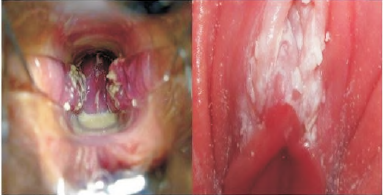

Paciente apresenta lesão genital bolhosa, múltipla,

com formigamento, ardor, vermelhidão e prurido

local, acompanhado de febre, disúria e astenia. O

aspecto local dessas lesões é compatível com a

imagem a seguir:

A paciente foi corretamente medicada com?

Mulher no menacme procura o ginecologista na UBS.

Ao exame físico, o médico encontrou o seguinte

cenário.

Qual o achado mostrado pela foto?

Paciente queixa-se de “dor e coceira nas partes”.

O exame físico foi compatível com a imagem a seguir:

Assinale qual sintomatologia deverá estar presente na história dessa infecção atual.